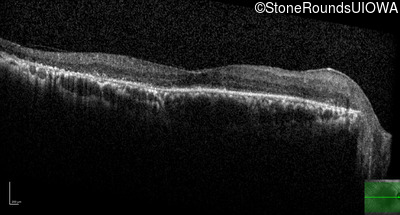

Age at visit: 71 years

Age at visit: 73 years

Age at visit: 75 years